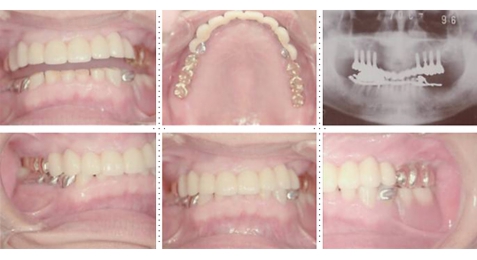

症例4

57才 女性

知人の歯科医からのご紹介。良く噛めない為、元気が出ない。介護の仕事を続けるためにも、歯を治療して自分がもっと元気になりたい。最初は部分的に治療する予定だったのですが、歯のない部分はインプラントを埋入し、最終的には上下顎全ての歯を治療し、しっかりものが噛めるようになりました。